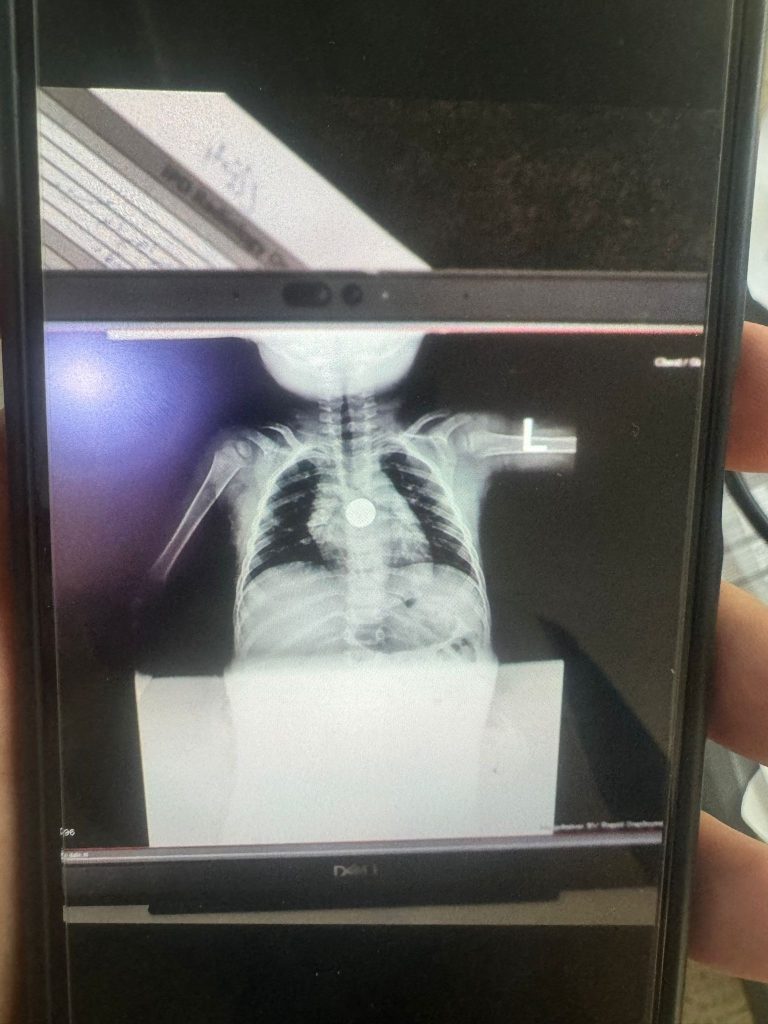

As increasing numbers of journalists in Gaza are killed by Israeli forces, Gazan health care workers and international medical volunteers serve as vital reporters bearing witness to the ongoing genocide.

The film follows Dr. Travis Meleen, an American anesthesiologist volunteering at Nasser Hospital in Gaza as he works with Palestinian surgical teams that continue training at Nasser Hospital even as the medical center is under siege. The film includes commentary from Omar El Akkad, an Egyptian-Canadian journalist and writer reporting on the genocide. He is the author of One Day, Everyone Will Have Always Been Against This.